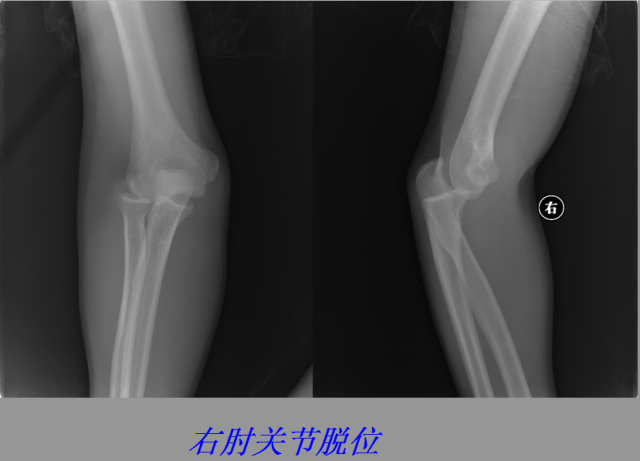

关节脱位篇

02

定义:关节脱位是暴力、关节感染、附近软组织挛缩或先天骨发育障碍造成的关节对位关系部分或完全脱离,即为半脱位或脱位。临床上以创伤性脱位*常见。